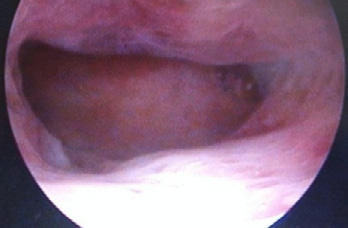

tabla elaborada por el autor, con datos de la historia clínicaDos meses después, la paciente consultó con ciclos regulares normales, manifestando interés en un nuevo embarazo y preocupación por la posibilidad de adherencias u otra alteración endometrial residual, producto de su cuadro clínico reciente, además de su antecedente de aborto espontáneo en el primer embarazo, que también ameritó legrado cuando cursaba 23 semanas; por todo lo anterior, se propuso realizar histeroscopia, la cual se practicó sin complicaciones, en fase folicular del ciclo, con técnica oficinal, encontrando cavidad de aspecto normal, ambos ostium vistos (figura 4a,4b,4c).